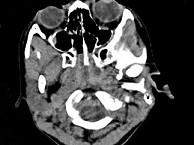

女,8岁,头痛,鼻塞半年余,CT如图所示,最可能诊断为 ( )A、神经纤维瘤B、咽后脓肿C、鼻咽部炎症D、腺样体肥大E、鼻咽癌

问题 女,8岁,头痛,鼻塞半年余,CT如图所示,最可能诊断为 ( )

选项 A、神经纤维瘤 B、咽后脓肿 C、鼻咽部炎症 D、腺样体肥大 E、鼻咽癌

答案 D